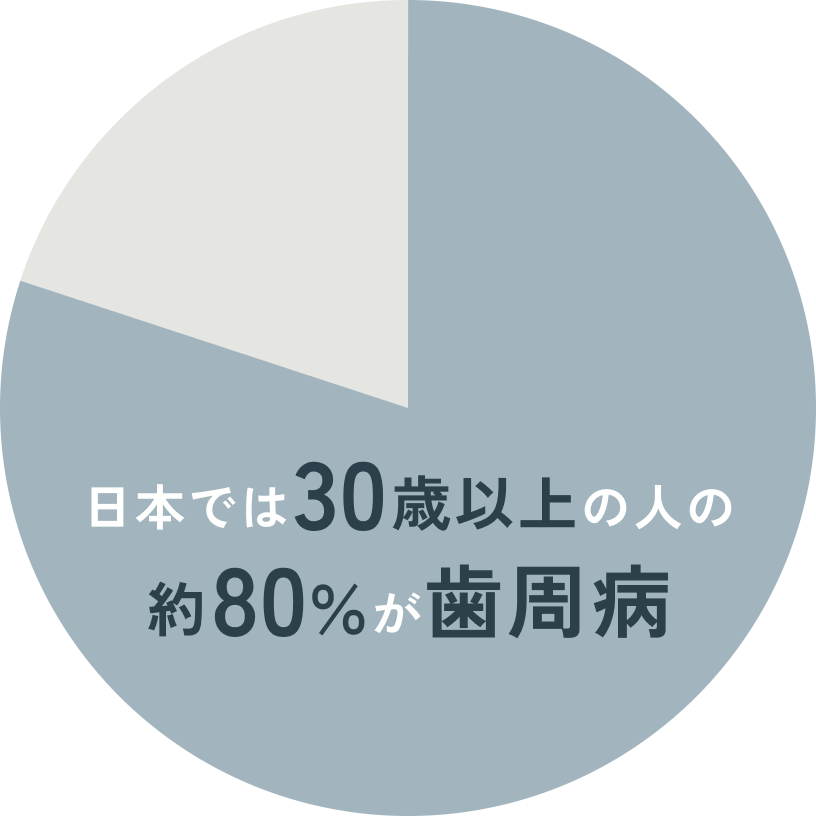

日本では30歳以上の人の約80%が歯周病に罹っています。もし、歯周病が進行して40代で歯を数本失うことになった場合、そこから先の長い人生、歯を失った状態で過ごさなければなりません。もちろん、入れ歯やブリッジ、インプラントといった治療で歯を補う治療をすることは出来ますが、いずれも費用がかかるか、他の健康な歯に負担をかけてしまうことになります。